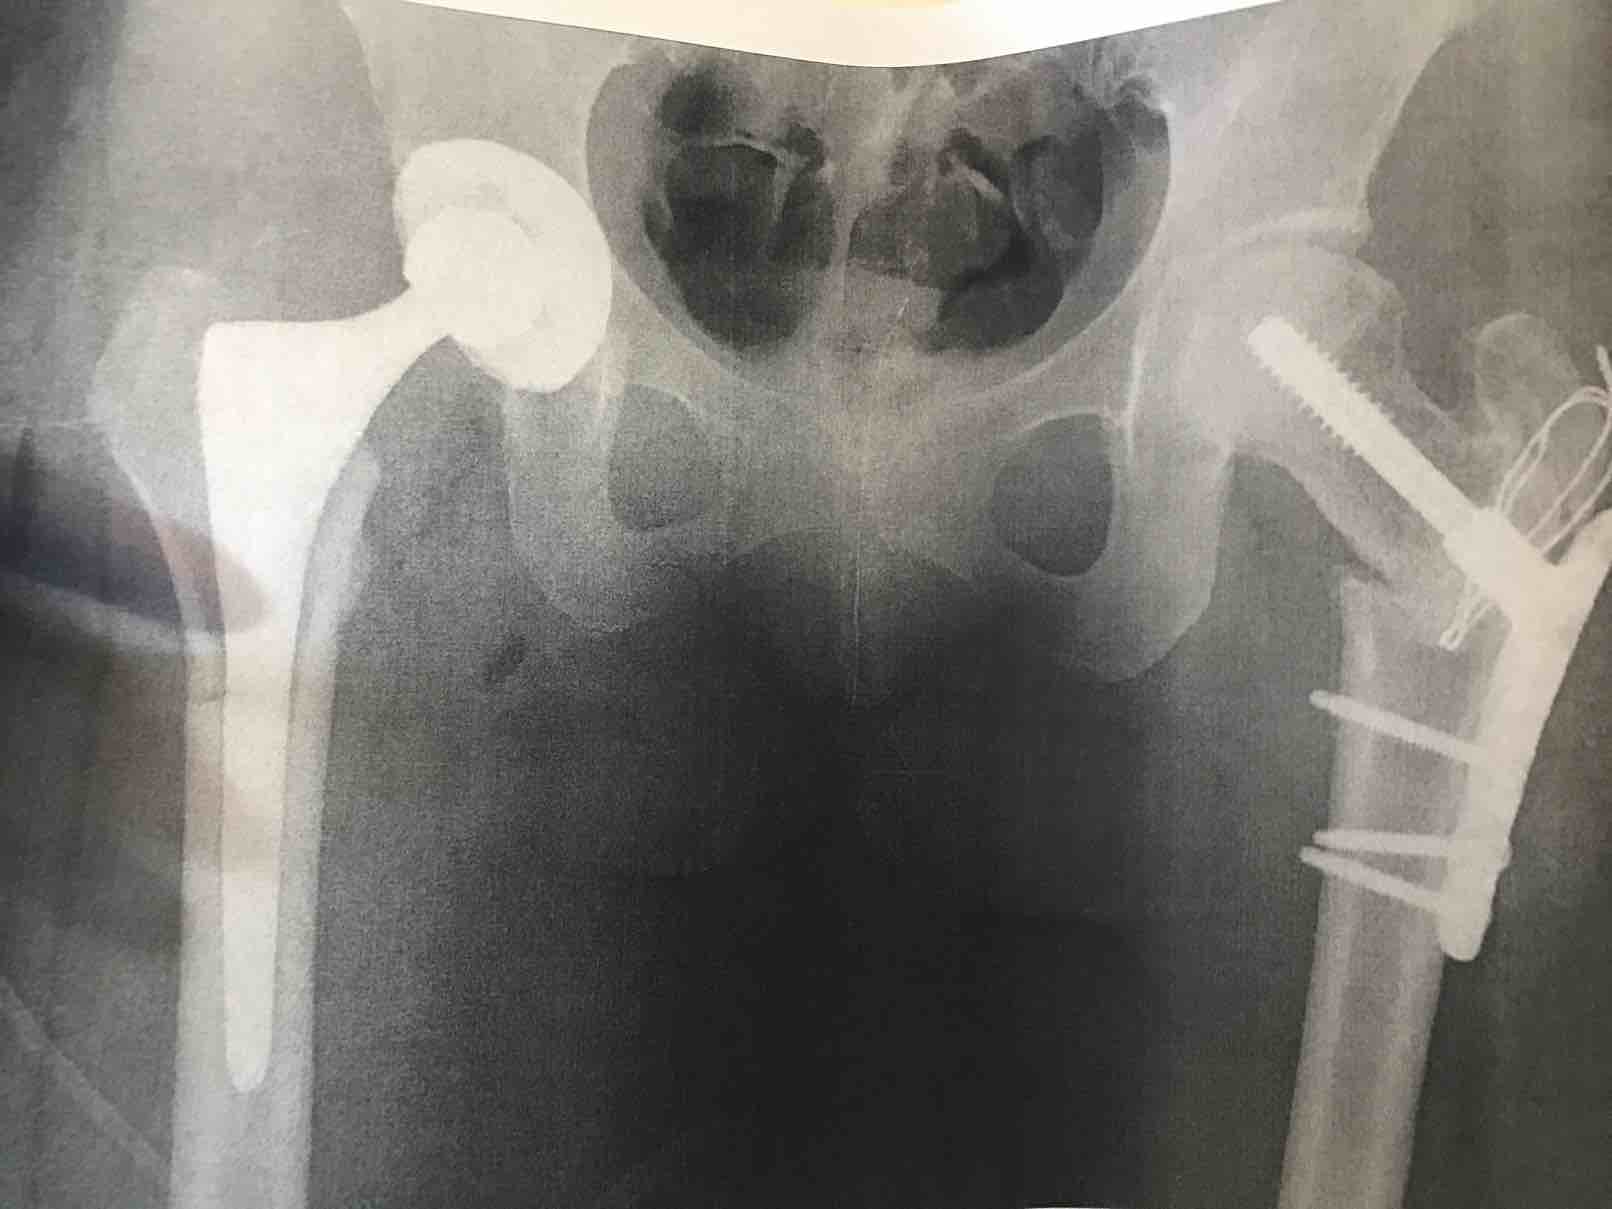

股骨头手术后第3天,昨天还疼的完全动不了,今天已经可以下床坐轮椅了。给大家附上一张检查结果,左边(这就是我们肉眼看到的右边,有缠着固定板的)是一月份动的骨移植手术,股骨头没有坍塌的情况下,骨移植是一个很好的选择,就是到恢复完全时间花的比较长,然后有负重限制,最初2个月只能负荷10公斤的体重,最后一个月才加到20公斤。右边股骨头置换手术是前两天做的,疼痛已经减少了很多。顺利的话10到14天就可以出院了。